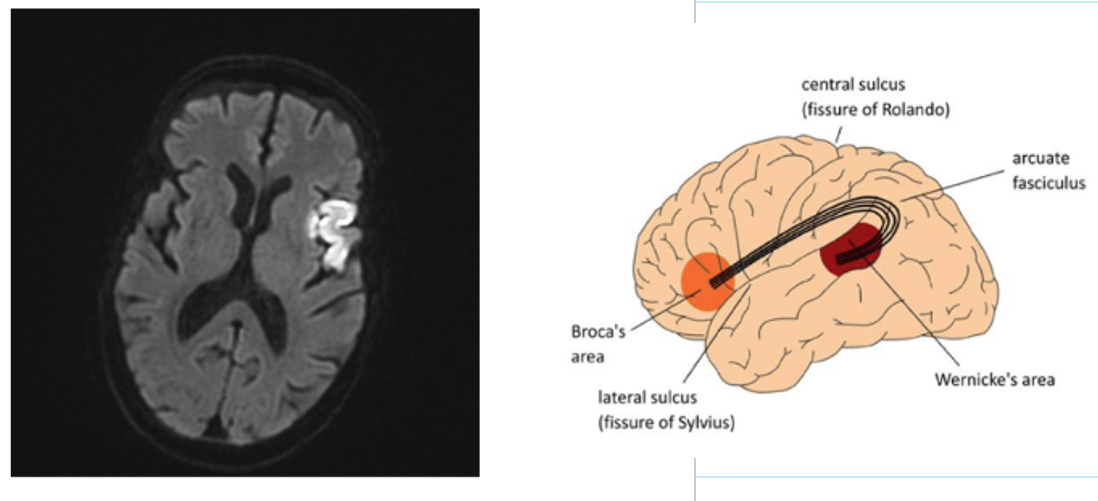

Why is this common with strokes?

Middle cerebral artery is the most common place for strokes to occur

Broca’s Aphasia

Difficulty expressing thoughts

May produce nonsense syllables, transpose words and utter structurally incorrect sentences

Language comprehension is mostly in tact

*Non-Fluent (limited production of speech)

*Agrammatism (delete words)

*Articulatory problems

Paraphasia (replace phoneme or word with another)

Automatic speech (overlearned utterances)